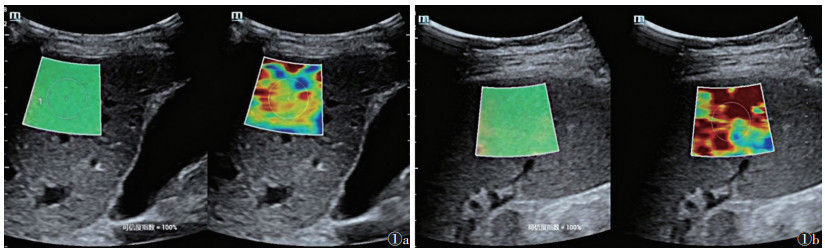

1.2.2 SWE常规超声检查后行SWE,测量LSM和SSM:①LSM测量。将探头垂直放置于右侧第7~9肋间,取样框放置于肝包膜下1~3 cm处,避开脉管系统,嘱患者呼气后屏气,待取样框填充>90%且图像稳定后测量3次,求平均值(图 1a)。②SSM测量。将探头置于左侧第9~11肋间,将取样框放置于脾包膜下0.5~2 cm处,测量方法同LSM(图 1b)。

| 注:图 1a为肝脏;图 1b为脾脏 图 1 肝脏硬度值(LSM)与脾脏硬度值(SSM)测量示意图 |